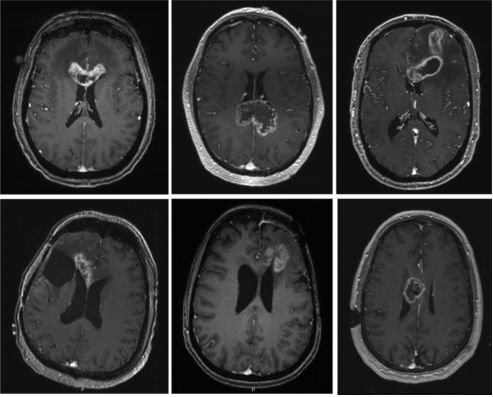

![]()

【杨宝慧】